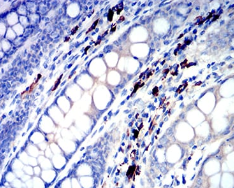

| AC2527 | IGLC2 Mouse Monoclonal antibody[5E12B] | 100ug | $367 | 10days |

| AC2527 | IGLC2 Mouse Monoclonal antibody[5E12B] | 200ug | $660.6 | 10days |